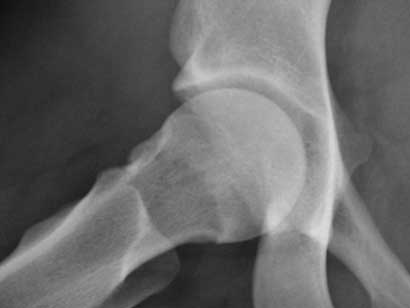

Hip arthroscopy

After femoral neck osteotomy

After femoral neck osteotomy.